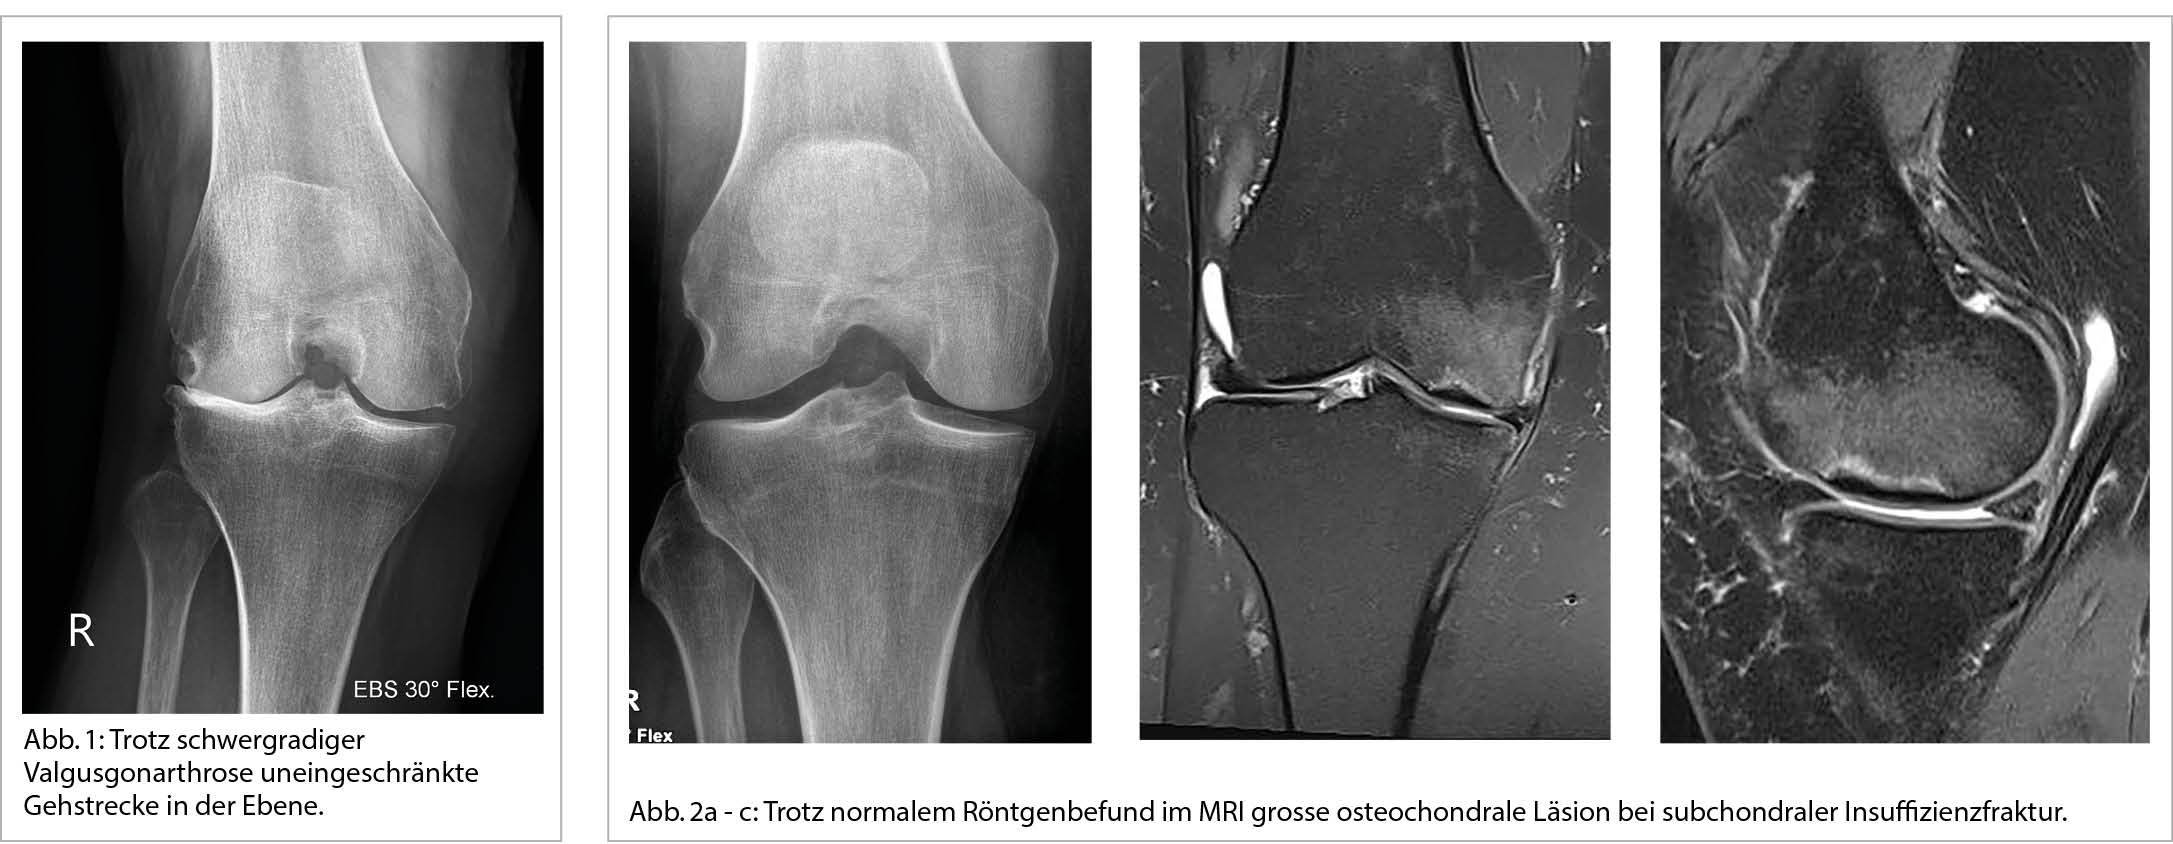

Das Krankheitsbild der Gonarthrose ist vielgestaltig. Vor der Behandlungsplanung gilt es abzuklären, in welchem Ausmass die einzelnen Gelenkkompartimente betroffen sind. Dafür sind die klinische und konventionell-radiologische Untersuchung oft ausreichend. Letztere ist nicht zwingend, zumal oft eine starke Diskrepanz zwischen der Klinik und den Röntgenbefunden besteht (Abb. 1). Zur radiologischen Beurteilung des femorotibialen Gelenkes eignen sich Aufnahmen im Einbeinstand am besten. Die Beinachse, die ligamentäre Stabilität und die muskuläre Führung sind immer mitzubeurteilen. Klinisch soll zudem geprüft werden, ob eine Aktivierung besteht, welche durch Ruheschmerzen, Schwellung, Erguss und Überwärmung charakterisiert ist. Auch die Erfassung einer sich durch myofasziale Druckdolenzen äussernden Periarthropathie ist wichtig. Gegenüber dem Röntgen erlaubt das MRI eine differenziertere Beurteilung des Knorpelschadens, des Zustandes der Menisken und nicht zuletzt auch des subchondralen Knochens. Vor allem bei plötzlichen starken Schmerzen und konventionell-radiologisch nur gering ausgeprägten Veränderungen hat das MRI einen hohen Stellenwert zur Erfassung osteochondraler Defekte, denen unter anderem subchondrale Insuffizienzfrakturen, die Osteochondritis dissecans oder auch die avaskuläre Osteonekrose zugrundeliegen können (Abb.2a - c). Manche dieser Pathologien erfordern spezifische therapeutische Massnahmen, insbesondere Entlastung. Das MRI ist auch bei Blockierungsphänomenen indiziert.